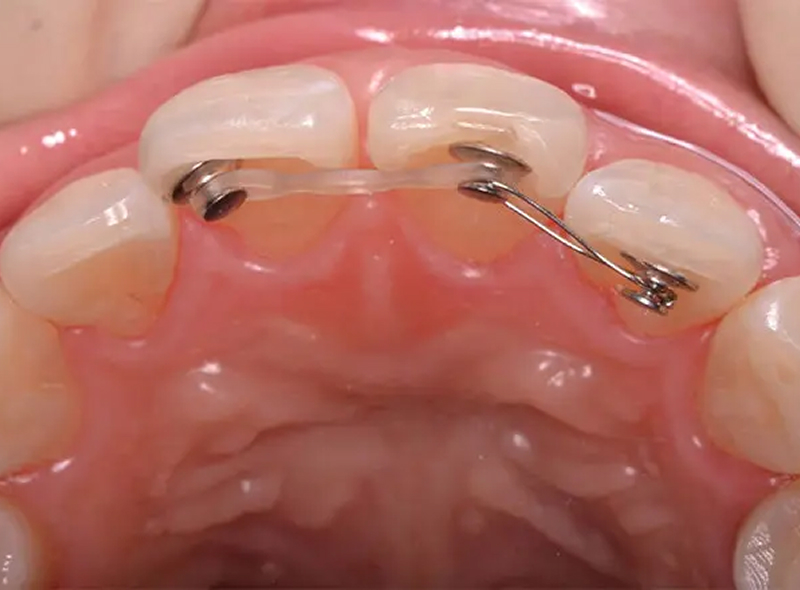

Case01抜歯する奥歯の代わりに親知らずを移動させた症例

右上第2大臼歯が歯髄炎で痛みがある状態でした。歯髄炎の治療はもちろんできますが、神経をとることになるので、歯の寿命は短くなります。そこで、戦略的に抜歯して、無垢の親知らず(第3大臼歯)を部分矯正で第2大臼歯の位置に持ってくる治療方法を提案しました。長期的に考えると良法ということが伝わり承諾していただけました。右上4本分に装置をつけ、親知らずを移動させました。若い方には特に意義深い治療となりました。

初診 2014.10.31

抜歯+矯正治療開始 2014.11.19

矯正治療の経過 2015.2.5

ファイナル 2015.3.13

| 主訴 | 右上1番奥歯がじっとしていても痛い |

|---|---|

| 診断 | 右側アングル1級、左側アングル2級の叢生 |

| 矯正方法 | 矯正用アンカーとマルチブラケットを用いた部分矯正 |

| 矯正期間 | 4か月・6回 |

| 費用 | 179,000円(税別) |

| 調整料 | 月1回 5,000円(税別) |